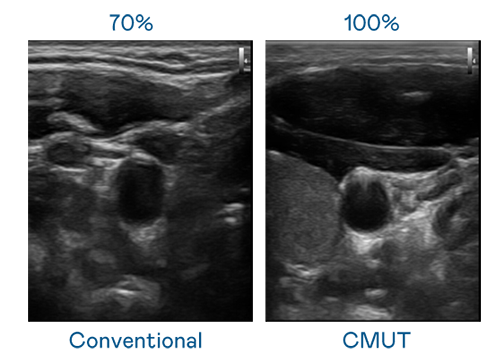

CMUT 技术是一种用电容式微机电元件来产生超音波讯号的技术。与传统 PZT 压电式技术相比,CMUT 频宽增加 30%,更宽频的超音波讯号让影像解析度大幅提升,是实现高影像品质医疗超音波扫描、促进精准医疗发展的关键技术。

大频宽带来超清晰影像

超音波影像的解析度高低,首先取决于探头能发出的讯号频宽。GGPoker CMUT 可提供高清晰的超音波讯号,提供高频宽、高灵敏度、影像纹理细节更高的超音波影像,协助医护人员缩短影像判读时间及利用精准的医疗影像进行诊断。